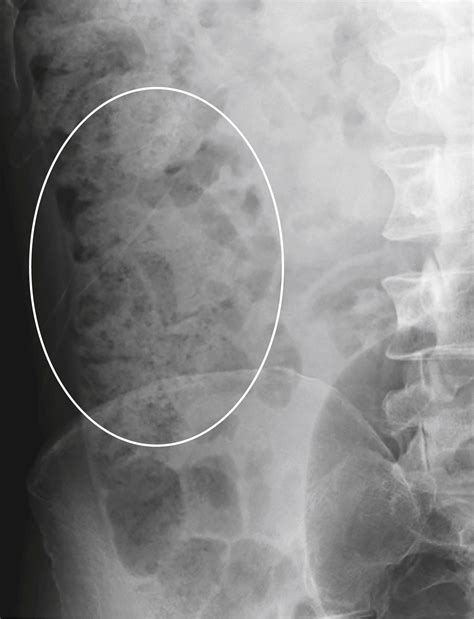

Understanding the internal health of your digestive system is crucial, and one term you might encounter during a clinical imaging report is a Moderate Stool Burden. This diagnosis, often provided after an X-ray or CT scan, indicates that there is a noticeable accumulation of fecal matter within the colon. While the term sounds clinical and perhaps concerning, it is a common finding in medical imaging that helps healthcare providers assess bowel habits and digestive functionality. Essentially, it suggests that your colon is holding more waste than what is considered optimal for standard transit, which can be a key indicator for issues such as chronic constipation or sluggish motility.

When a radiologist identifies a Moderate Stool Burden, they are observing the density and distribution of feces within the large intestine. Unlike a severe impaction—which represents a medical emergency where the bowel is completely blocked—a moderate burden is often interpreted as a “backed-up” state. It means that the waste is moving through the digestive tract slower than it should, but it has not reached a point of complete obstruction.

This finding is often subjective, based on the radiologist’s interpretation of the scan. It serves as a diagnostic tool rather than a final disease diagnosis. It prompts doctors to look closer at your medical history, current symptoms, and lifestyle factors to determine if an underlying condition is preventing regular evacuation.